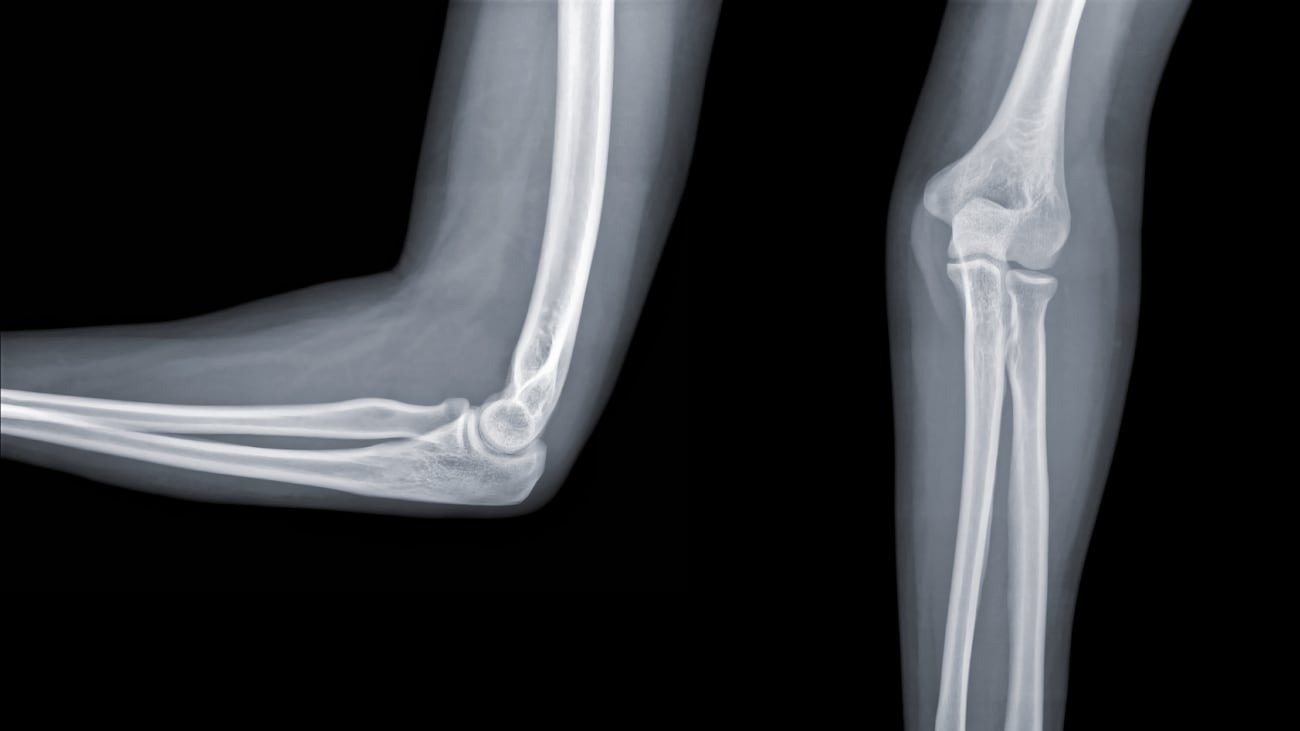

Terrible Triad Injuries and the Complex Elbow: Anatomy and Biomechanics

Neil S. Tarabadkar, MD, discusses elbow dislocations, historical analysis, current concepts and diagnostics surrounding the topic of triad injuries.